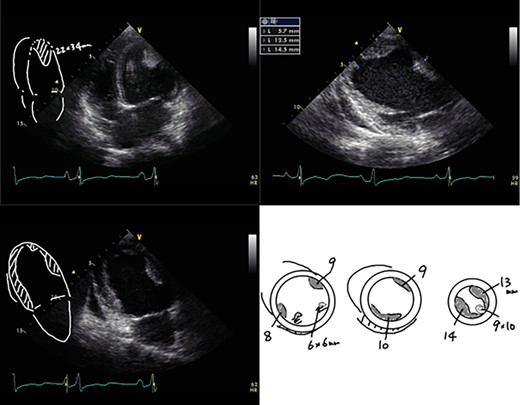

A 23-year-old woman presented with dyspnea after giving birth to her second child at a local hospital. Edema of both lower limbs gradually appeared, her labored breathing worsened, and the left ventricular ejection fraction (LVEF) was <30% by echocardiography. She was diagnosed with PPCM 5 months after childbirth. The LVEF had decreased to 10% and a left ventricular apical thrombus was also observed by echocardiogram (Fig. 1). She was transported to our institution due to progressive severe heart failure, and treated with intravenous inotropes, extracorporeal membrane oxygenation (ECMO) and intra-aortic balloon pumping (IABP). The LVEF subsequently decreased to 7% and left ventricular enlargement with multiple mural thrombi was observed. The condition was INTERMACS profile 1, and a LVAD was indicated. In Japan, an implantable LVAD can be applied only in patients in whom registration for heart transplantation has been already approved and the patient had no chance for an implantable LVAD. Thus, we implanted an external LVAD (AB 5000, ABIOMED, Danvers, MA, USA).